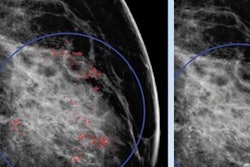

"One big advantage of the network we used is that it generates heat maps that highlight what the neural network sees as suspicious," he told session attendees.